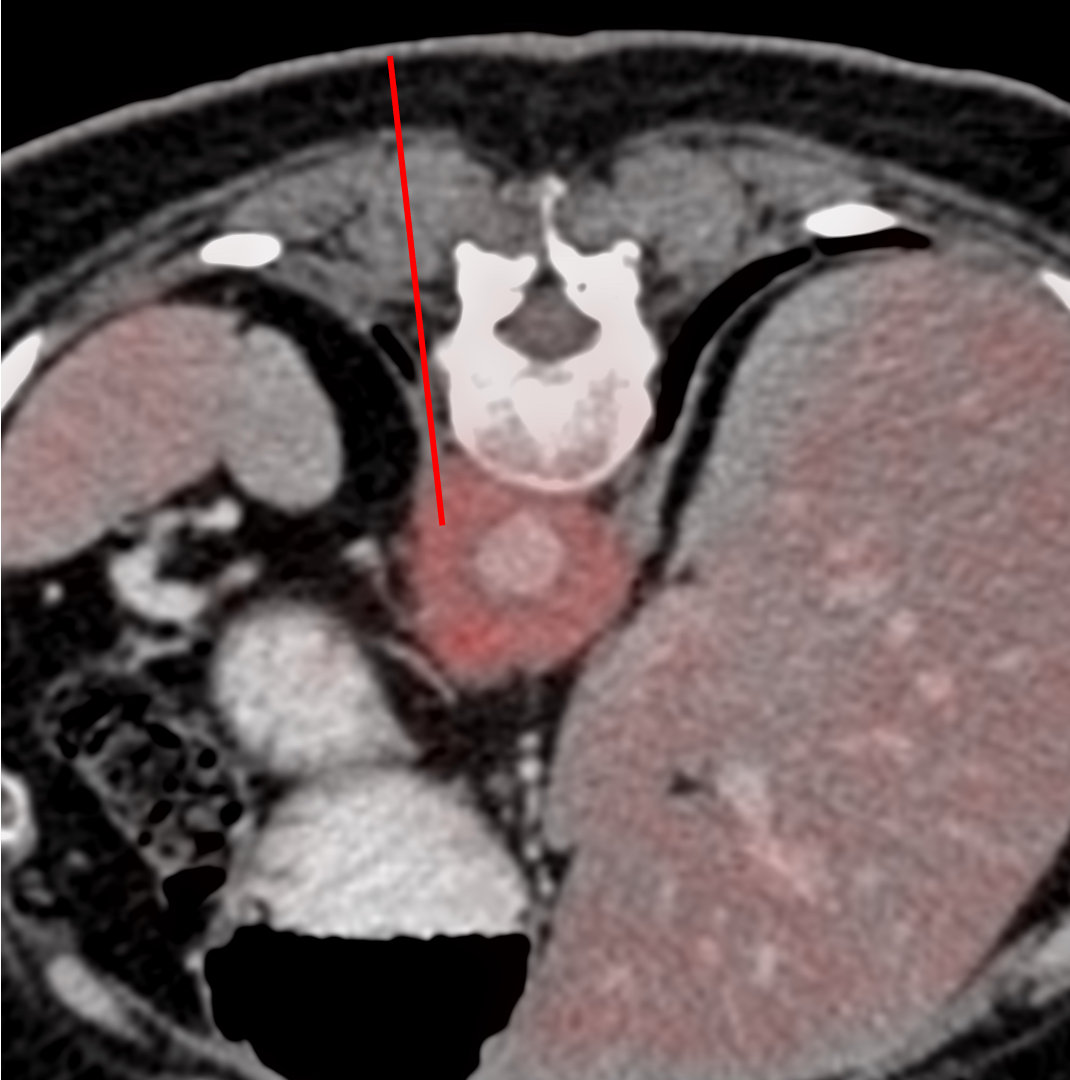

Biopsy of retroperitoneal fibrosis is possible under CT guidance

I decided to use a prone approach from the left.